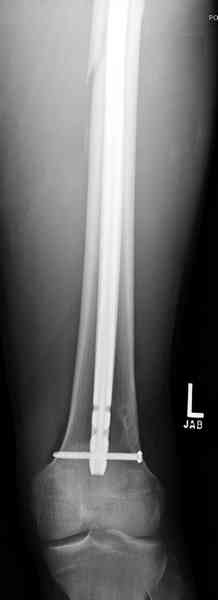

В нашем случае 21 летний боец уличного фронта, фиксацию провели на следующий день, зафиксирован интрамедуллярным штифтом. Не стали делать первичную хирургическую обработку точечной раны, зафиксирован как есть. Клинические снимки:

Конечно, наш случай не эталон, возможно, на месте вам виднее, может быть, нет необходимости ориентироваться на зарубежные ссылки, если получается лечить аппаратом Илизарова на месте, почему нет? Необходимо посмотреть собственный арсенал, чем фиксировать, и какая теория, иначе любой отличный метод можно превратить в источник остеомиелита.